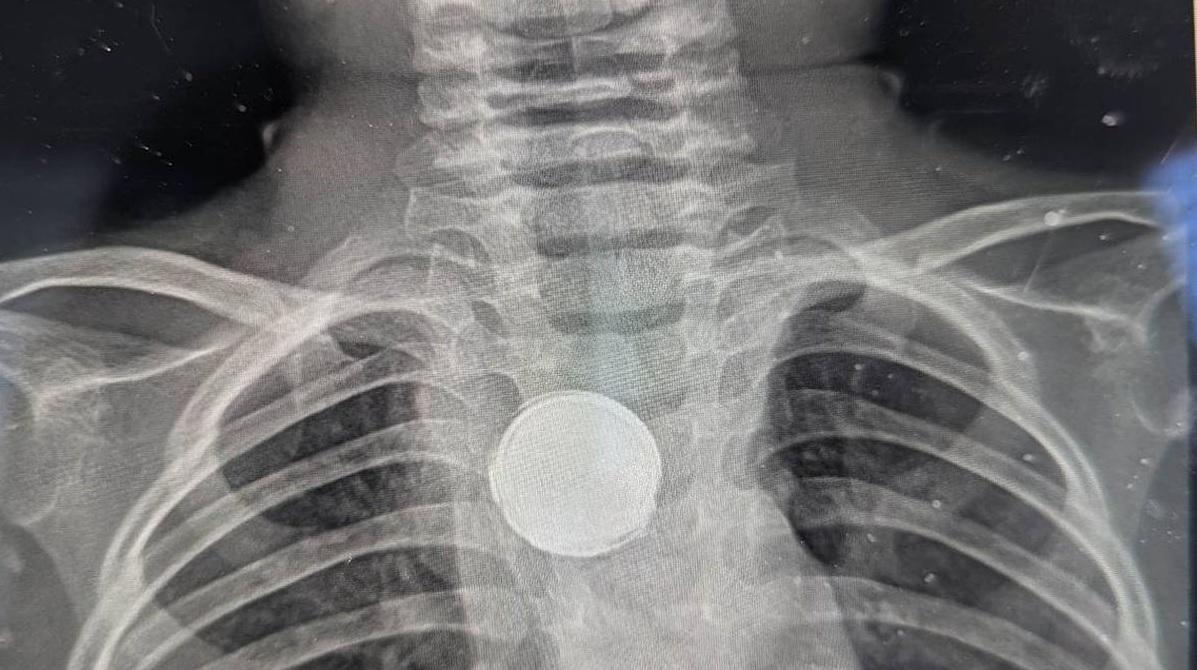

X光檢查發現盧克食道裡有異物(左),醫生將其取出,發現是膠帶包住的鈕扣電池(右)。(互聯網)

母親帶盧克去看另一兒科醫生,詎料經X光檢查後,發現食道裡有一鈕扣形異物。醫生單看X光影像,起初排除是鈕扣電池,因為一般來說,電池卡在食道,僅兩小時就會腐蝕組織,「所以不可能是電池」。

然而,醫生其後動手術把異物取出,卻驚見確是一粒鈕扣電池,由黑色絕緣膠帶包著。估計電池卡在盧克食道已長達5個星期,醫生推斷,外層的膠帶防止電池腐蝕,救了盧克一命,但食道組織仍有損傷,需動手術重建並擴大食道。

鈕扣電池卡在食道裡。(互聯網)